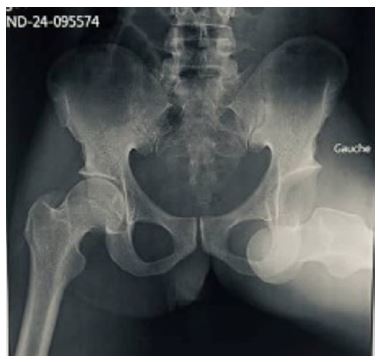

Radiographic control using an image intensifier confirmed reduction without associated bone lesions or intra-articular fragments (Figure 4), as did a control radiograph of the front pelvis at D2 (Figure 5).

Figure 5: Front view of pelvis after orthopedic reduction.